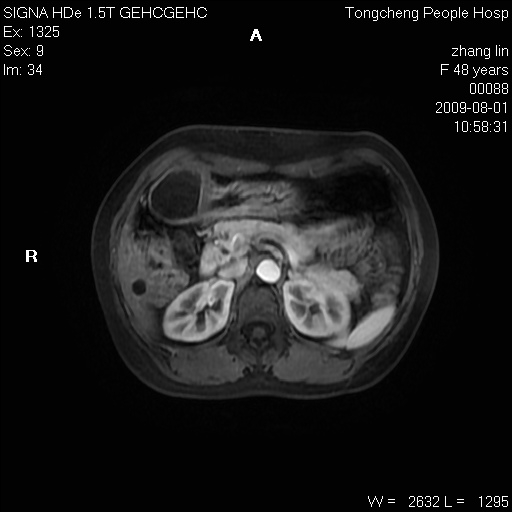

女,48岁。健康体检,彩超发现右肾占位性病变。平素健康。

临床诊断:右肾占位性病变,性质待定(囊肿?肿瘤?)。

上中腹部mr平扫+增强扫描,图像如下:

右肾上极见一类圆形病灶,t1wi呈等信号t2wi呈等高混杂信号,三期增强无强化,边界清---考虑囊肿出血。

同反相位均表现为等信号,病变无强化,考虑含蛋白的囊肿可能,弥散加权相或许有些帮助,